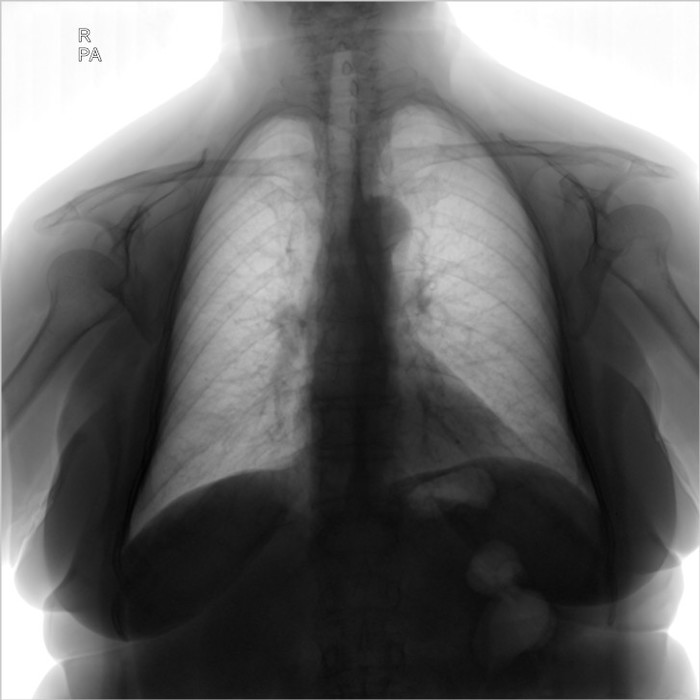

Здравствуйте, я работаю лаборантом в рентген кабинете, в госпитале, в Ливий. К сожалению у нас нет рентгенолога, и в некоторый случаях мне приходиться "читать" снимки самому... Со мной вместе работает мама, она медсестра в реанимаций. Ей сейчас 67 лет, решил сделать ей рентген лёгких, на боли в груди она не жалуется. Я начал изучать снимок и увидел образование в форме круга в левом легком возле бронха, подскажите мне пожалуйста что это такое и стоит ли мне беспокоится. Фото в негативе и позитиве прилагаю ниже.